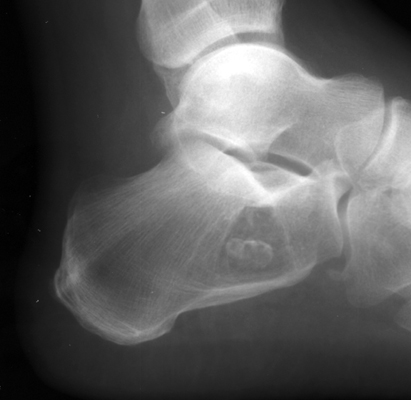

Intraosseous lipoma

A classic appearance of intraosseous lipoma of the calcaneus is the presence of a well defined lytic lesion with a central calcification resembling a cockade. A cockade is badge, usually in the form of a rosette, or knot, and generally worn upon the hat.

Lateral foot - Click on the image for a larger version